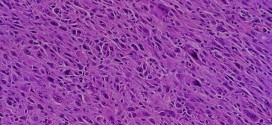

El fibrosarcoma. Tumor maligno constituido por células fusiformes (en forma de hueso) sin otra diferenciación celular, con colágeno y fibras de reticulina (sustancia albuminoidea de las fibras conjuntivas del tejido reticular) abundantes. Produce metástasis principalmente por vía hematógena. El Fibrosarcoma es un tipo de tumor maligno que se desarrolla a menudo en los extremos de los huesos de la pierna y …